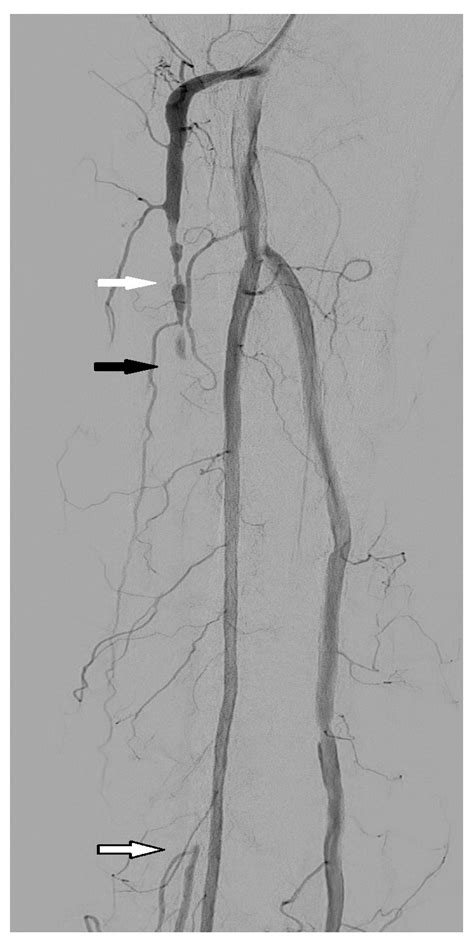

The DSA medical abbreviation stands for Digital Subtraction Angiography. This is a diagnostic imaging technique used to visualize blood vessels in the body. DSA is particularly valuable in identifying blockages, aneurysms, and other vascular abnormalities. The procedure involves injecting a contrast dye into the blood vessels, which is then imaged using X-ray technology. The digital subtraction process enhances the visibility of the vessels by subtracting background structures, providing a clear view of the vascular system.

• Vascular Surgery: Surgeons use DSA to plan and execute procedures for peripheral artery disease, aortic aneurysms, and other vascular issues.

• Case Study 3: Peripheral Artery Disease: A patient with peripheral artery disease undergoes DSA to assess the extent of blockages in the leg arteries. The procedure helps in planning a bypass surgery to restore blood flow.